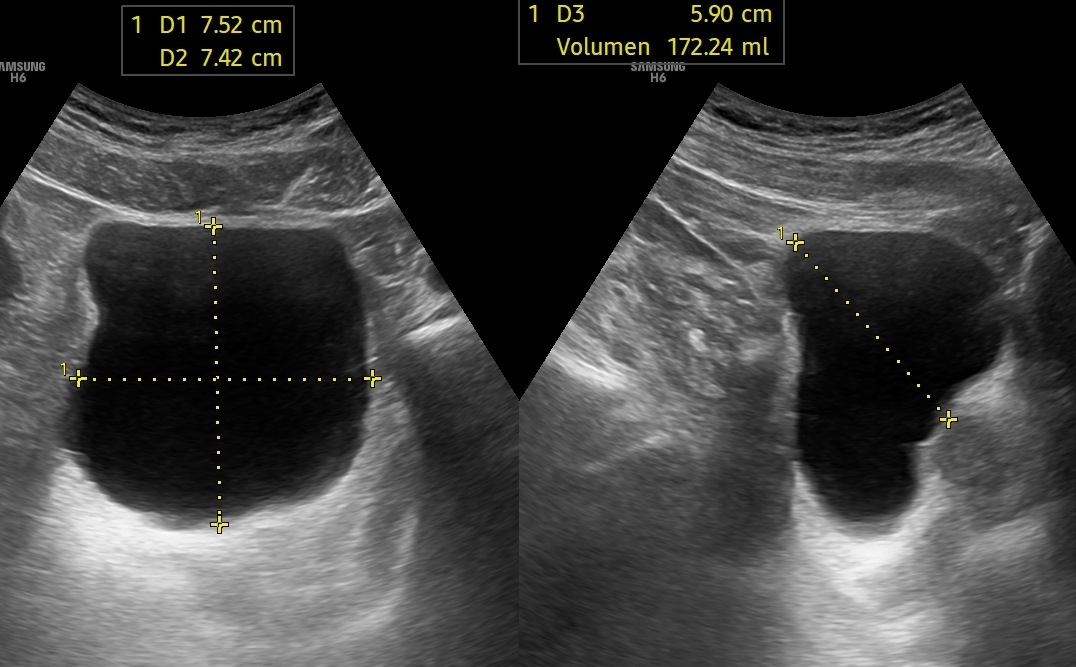

Persistiendo el dolor, se realiza ecografía clínica objetivándose: vejiga con abundante contenido urinario, con sensibilidad a la palpación y sin deseo miccional. Riñones de morfología y ecoestructura normal, sin signos de hidronefrosis. Hígado y vesícula sin alteraciones, sin litiasis y Murphy ecográfico negativo.

Ante los hallazgos, se plantea la posibilidad de retención aguda de orina (RAO). Este caso ilustra cómo la presentación clínica de la RAO puede simular un cólico nefrítico u otras causas de dolor abdominal agudo.

La ecografía clínica resultó decisiva al identificar una vejiga distendida sin signos de obstrucción a nivel renal, permitiendo un diagnóstico rápido y un tratamiento inmediato.